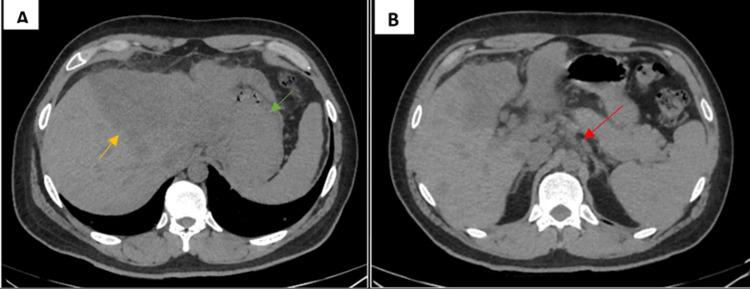

Cholangiocarcinoma (CCA) is an uncommon biliary neoplasm that is more frequent in male patients. CCA is categorized into intrahepatic cholangiocarcinoma (iCCA) and extrahepatic cholangiocarcinoma (eCCA) associated with the anatomical origin location. The clinical presentation is non-specific and varies depending on the origin, iCCA is generally asymptomatic until advanced disease is present therefore this neoplasm presents a poor prognosis with a survival rate of two years. We present a case of iCCA with lung metastasis in a 29-year-old male patient with no risk factors for this malignancy.

胆管癌(CCA)是一种不常见的胆道肿瘤,在男性患者中更为常见。CCA根据解剖学起源部位分为肝内胆管癌(iCCA)和肝外胆管癌(eCCA)。其临床表现不具有特异性,且因起源部位而异,iCCA在疾病进展之前通常无症状,因此这种肿瘤预后较差,生存率为两年。我们报告一例29岁男性iCCA伴肺转移的病例,该患者无此恶性肿瘤的危险因素。